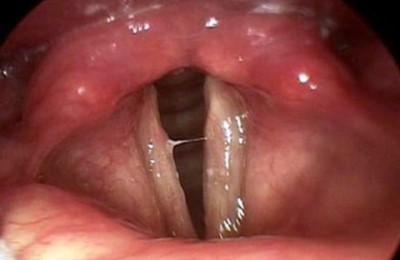

Пациент 11 лет, был направлен на прием к лору с жалобами на затрудненное дыхание, сухость в горле и осиплость голоса. При осмотре: общее состояние ребенка не нарушено, слизистая гортани гиперемирована, отечна, голосовые складки розовые, смыкаются не полностью. Диагноз: катаральный острый ларингит.

Назначено лечение: голосовой покой, диета, гортанные заливки с масляным раствором витамина Е, щелочные ингаляции и Эфизол (пастилки для рассасывания).

Через неделю состояние ребенка нормализовалось и он вернулся к привычному образу жизни.